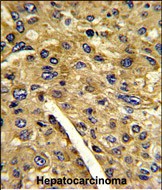

- Formalin-fixed and paraffin-embedded human hepatocarcinoma reacted with AMT Antibody (N-term), which was peroxidase-conjugated to the secondary antibody, followed by DAB staining. This data demonstrates the use of this antibody for immunohistochemistry; clinical relevance has not been evaluated.